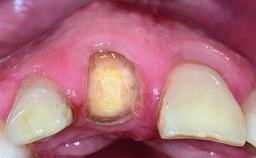

Replacement of a Compromised Upper Right Central Incisor: Hard- and Soft-tissue Augmentation, Late Placement of an RC Bone Level Implant

A 36-year-old male patient with a compromised maxillary central incisor was referred by his general dentist for consultation. The patient’s chief complaints were the gradual debonding of a temporary crown on the right central incisor and unsatisfactory esthetics due to an increasing diastema between the right central and lateral incisors. The patient reported a traumatic event some years previously, when a crown had been placed after root-canal treatment. The referring dentist wanted to provide a new crown restoration, but was concerned about the condition of the residual root. Anamnesis was negative for any other dental or periodontal pathology in the remaining dentition. The patient reported taking no medications: He was a smoker (10 to 15 cigs/day) and had realistic esthetic expectations.

Soft Tissue Contour and Volume Slightly compromised